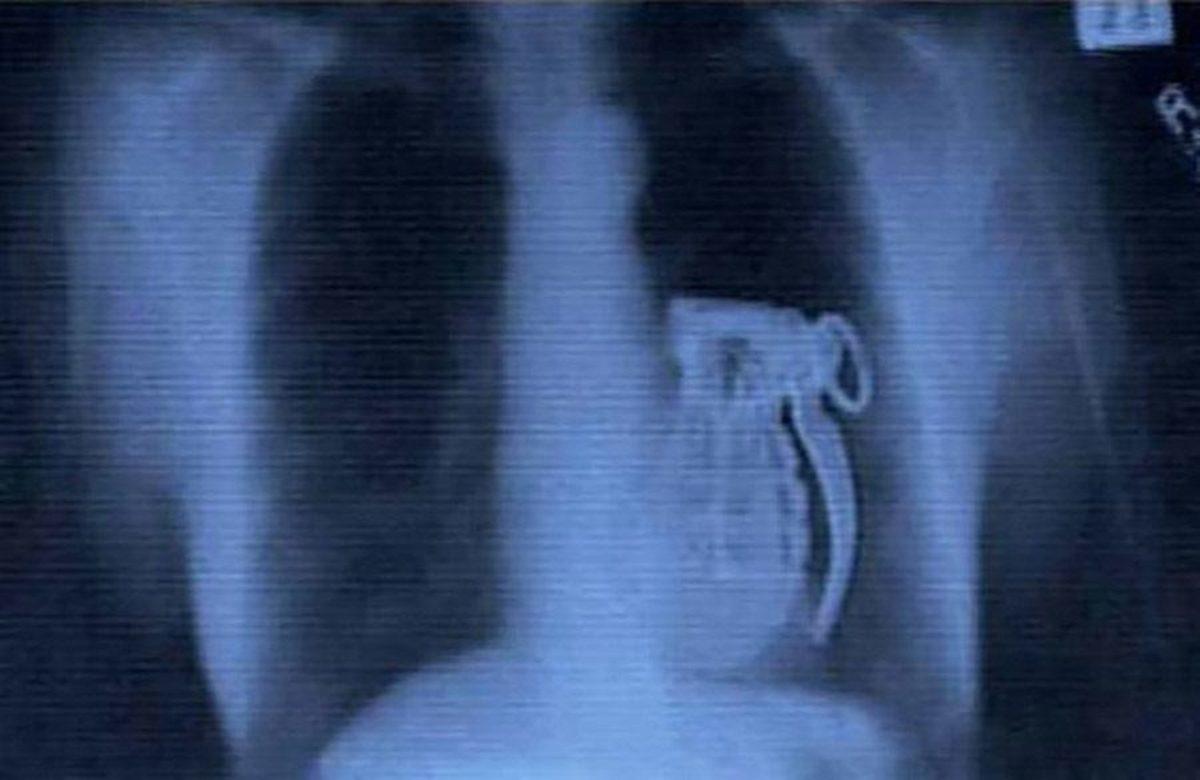

- El bombası yutan bir terörist. Bilmediği şeyse pimini çekmeden yuttuğu için asla patlatılamayacağıydı.

- Bir Kolombiyalı askerin yüzüne giren bomba.

Ameliyathanede patlamasından korktukları için hastanenin otoparkında sağlık personeli tarafından başarıyla çıkarılmış.